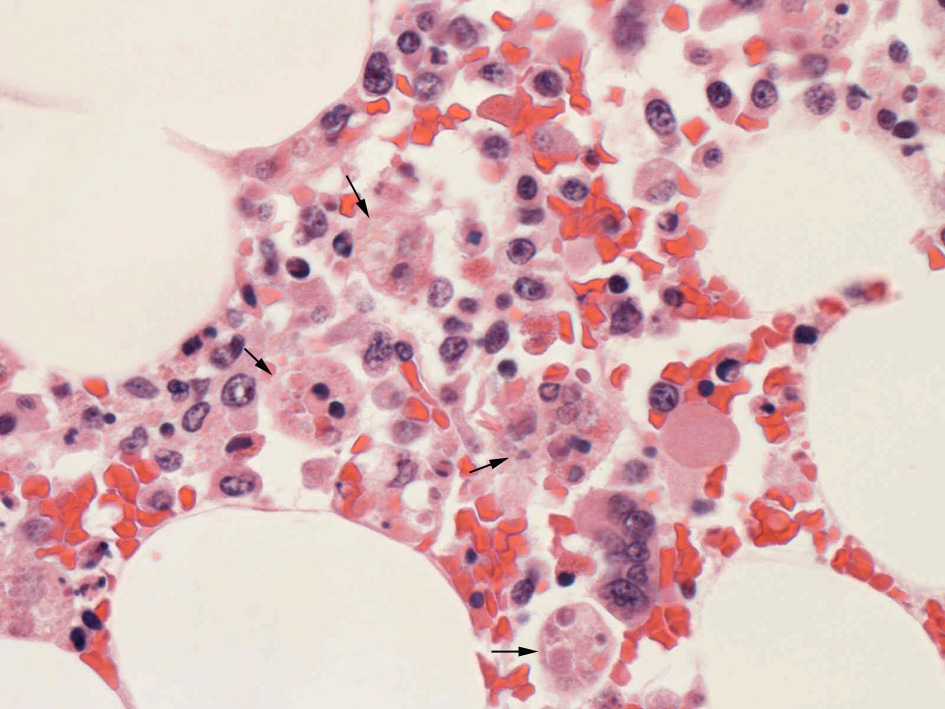

数年前、ナヨンちゃんは「血球貪食性リンパ組織球症」と言う難病を診断されたそうです。

入院して治療を受けましたが、一ヶ月もたたないうちに、ナヨンちゃんは空の星となりました。

抗がん治療が切実な病気ですが、癌とはその疾病コードが異なるため、ナヨンちゃんとその家族は保険料を受け取ることができなかったそうです。お母さんは、この病気と関連して、大統領官邸宛に「国民請願」を揚げたこともあります。

その請願の内容は、「血球貪食性リンパ組織球症」の疾病コードを変えてほしいという趣旨の文章でした。